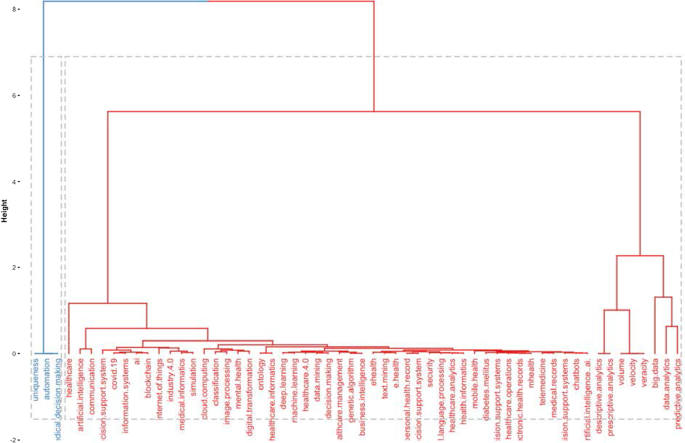

This section aims to strengthen the research scope by answering RQ3: What are the research applications of artificial intelligence for healthcare?

Benefiting from the topical dendrogram, researchers will provide a development model based on four relevant variables [ 69 , 70 ]. AI has been a disruptive innovation in healthcare [ 4 ]. With its sophisticated algorithms and several applications, AI has assisted doctors and medical professionals in the domains of health information systems, geocoding health data, epidemic and syndromic surveillance, predictive modelling and decision support, and medical imaging [ 2 , 9 , 10 , 64 ]. Furthermore, the researchers considered the bibliometric analysis to identify four macro-variables dominant in the field and used them as authors' keywords. Therefore, the following sub-sections aim to explain the debate on applications in healthcare for AI techniques. These elements are shown in Fig. 12 .

Dominant variables for AI in healthcare.

Health services management

One of the notable aspects of AI techniques is potential support for comprehensive health services management. These applications can support doctors, nurses and administrators in their work. For instance, an AI system can provide health professionals with constant, possibly real-time medical information updates from various sources, including journals, textbooks, and clinical practices [ 2 , 10 ]. These applications' strength is becoming even more critical in the COVID-19 period, during which information exchange is continually needed to properly manage the pandemic worldwide [ 71 ]. Other applications involve coordinating information tools for patients and enabling appropriate inferences for health risk alerts and health outcome prediction [ 72 ]. AI applications allow, for example, hospitals and all health services to work more efficiently for the following reasons:

Clinicians can access data immediately when they need it.